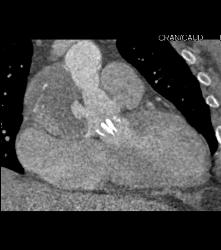

Pseudo-aneurysm Arises Off Aortic Root